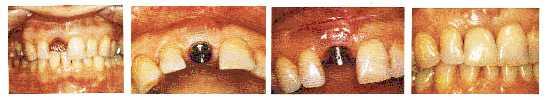

人工种植牙是现代治疗牙齿缺失的最先进镶牙技术(被称为人类的第三副牙齿)。

就是在缺牙区植入钛金属的人工牙根,待人工牙根与周围骨组织形成“骨结合”后,就可以镶上一颗理想牙齿。其形态、功能,犹如天然牙齿一样。自然美观。

感觉舒适,自然美观,形态逼真。